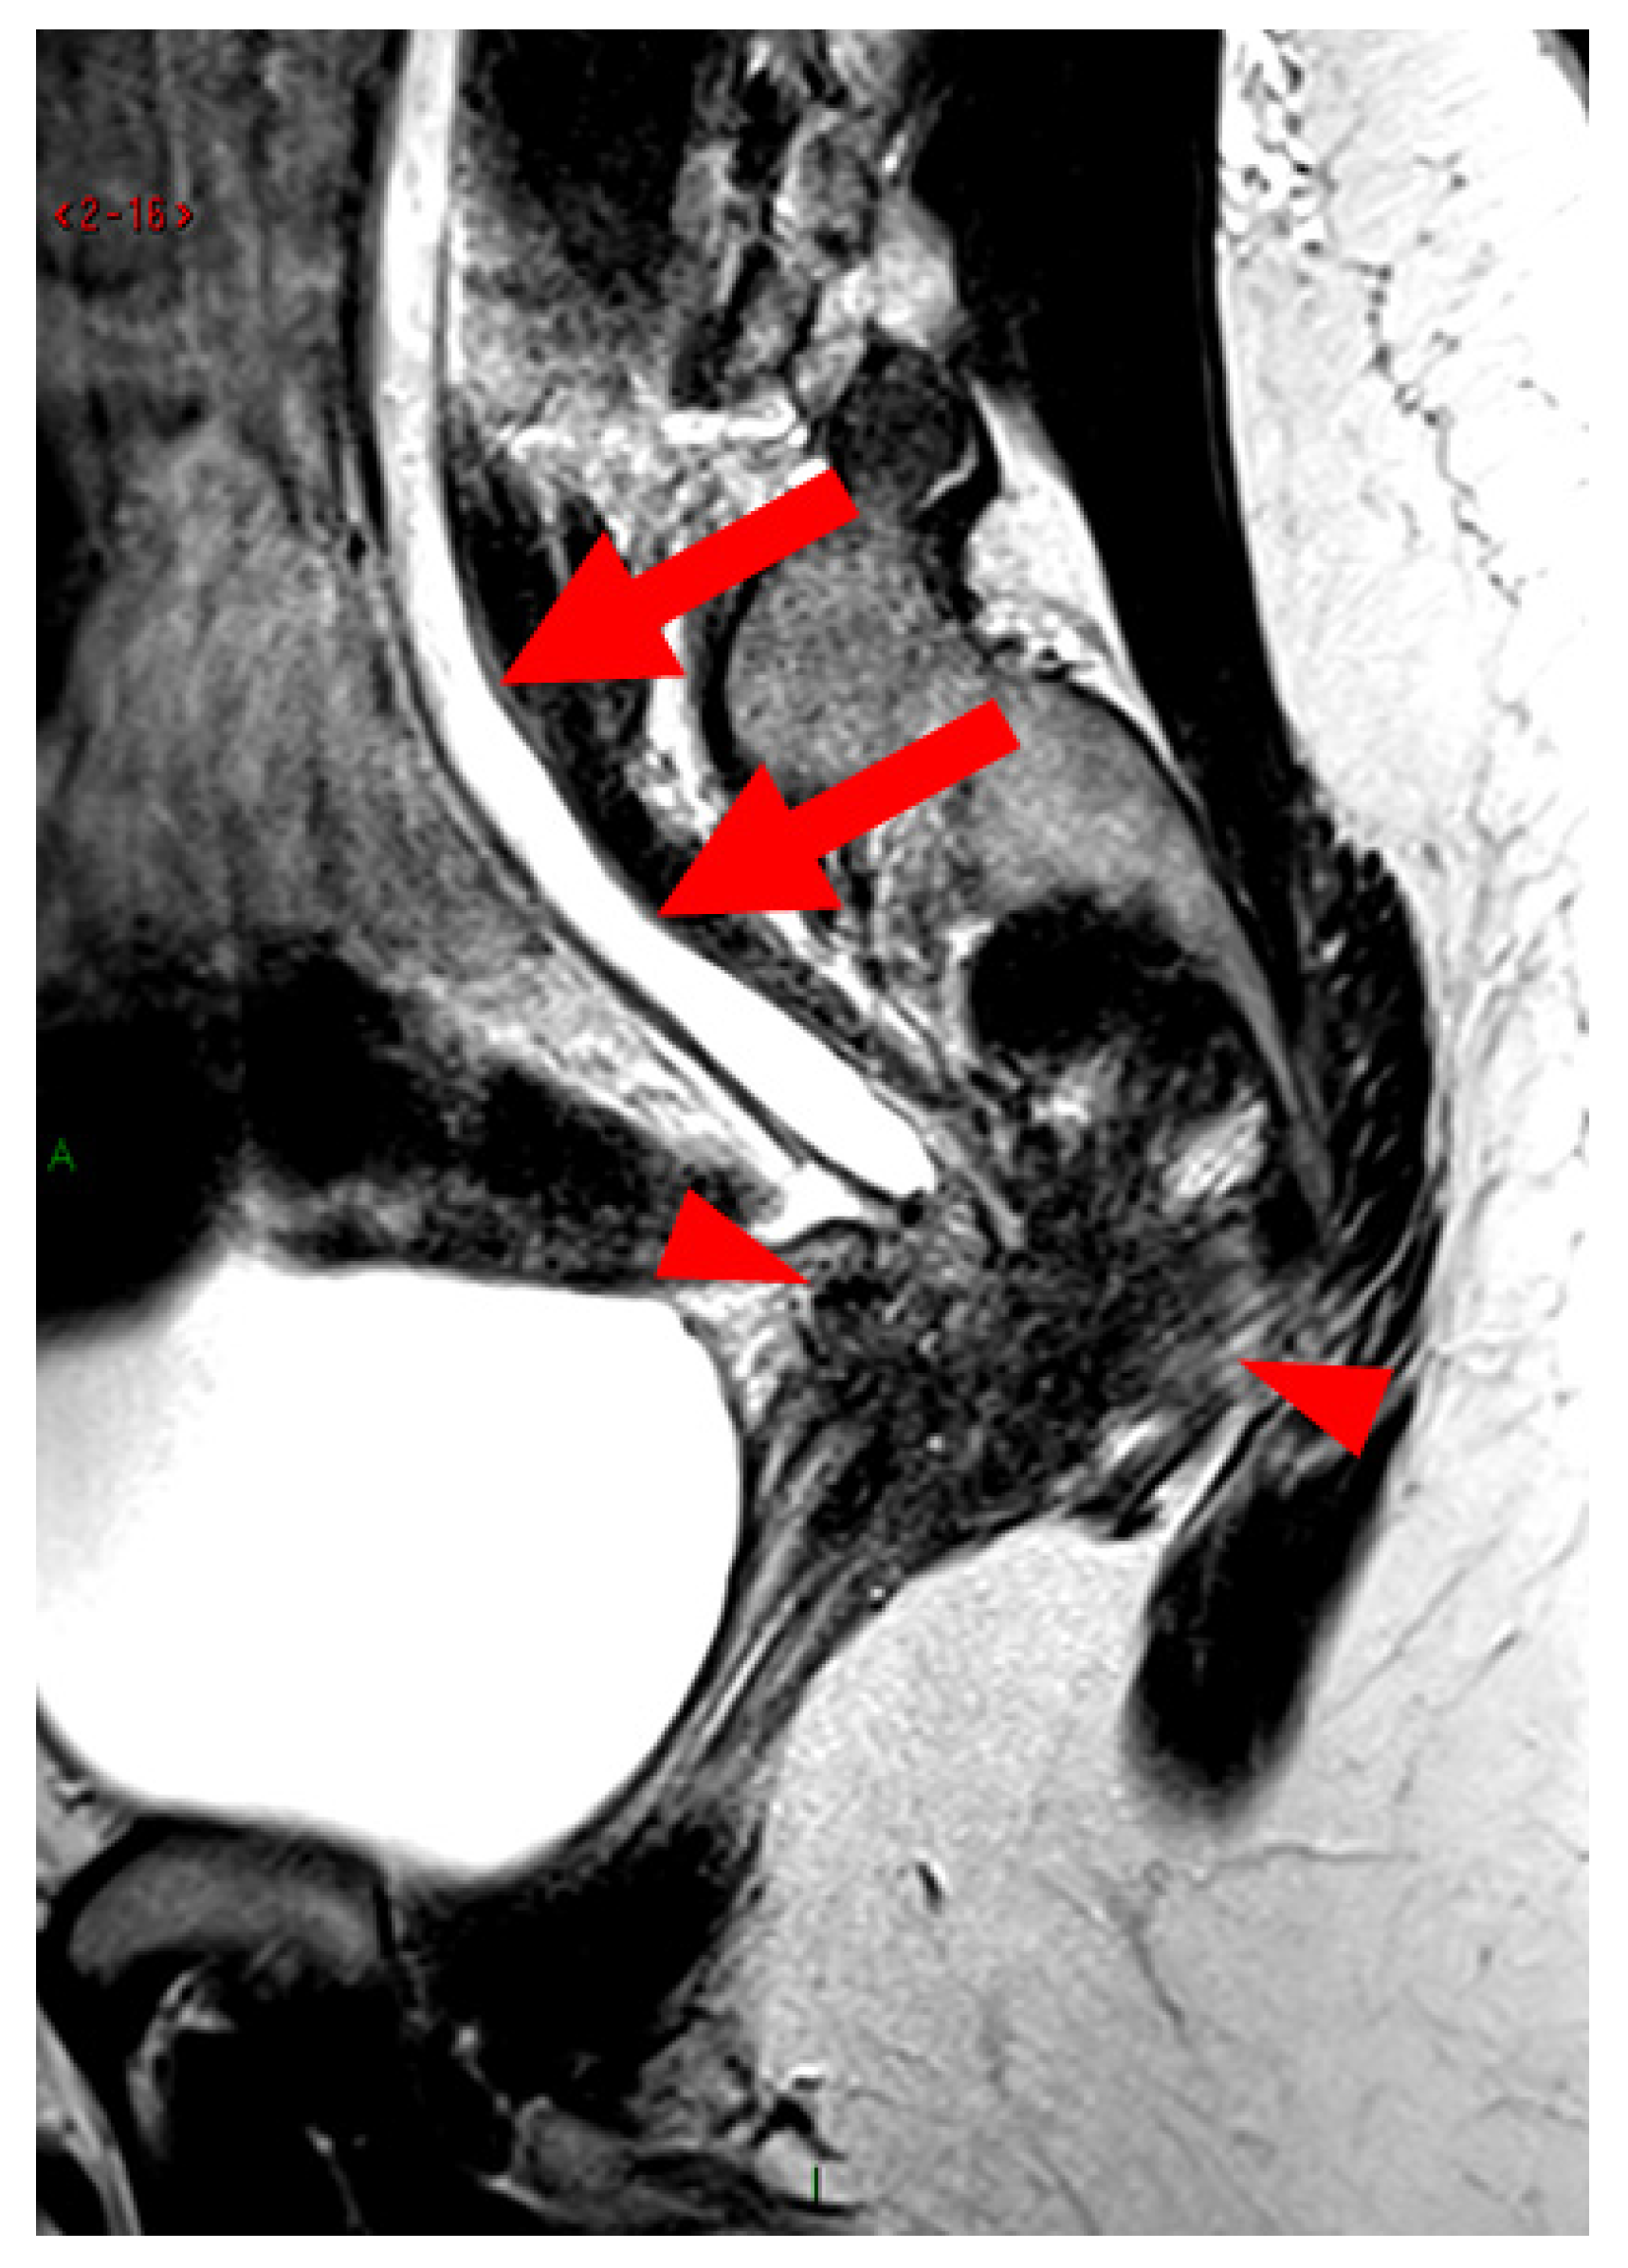

A type 6 USL is associated with adjacent pelvic “visceral” involvement in a broad sense. It most commonly affects the digestive tract (Figure 8 and Figure 9), with the rectum and rectosigmoid junction wall thickening: in this case, the lesion often appears as a “medallion-shaped” protrusion into the lumen. Less frequently, the urinary tract is affected (Figure 9 and Figure 10), involving the muscular layer of the bladder or even the distal ureter at the level of the common iliac artery, with stenosis potentially leading to upstream hydronephrosis. More rarely, as USLs are also close to nearby pelvic nerve structures (Figure 11), contiguous involvement of the inferior hypogastric plexus located in the sacro-recto-genital septum (a.k.a. Delbet sagittal fascia) beneath the distal two-thirds of the USL, or exceptional involvement of the sciatic nerve adjacent to the pelvic wall, is possible (Figure 12, Figure 13 and Figure 14).

Figure 10. Pelvic MRI scan of a patient with HTD type 6 USLs. Sagittal T2WI demonstrates nodulospicular infiltration of the sacro-recto-genital septum, with the endometriotic lesion delineating the structure of the inferior hypogastric plexus (arrowheads). Note that the lesion also involves the distal ureter, causing upstream ureteral dilation (arrows).